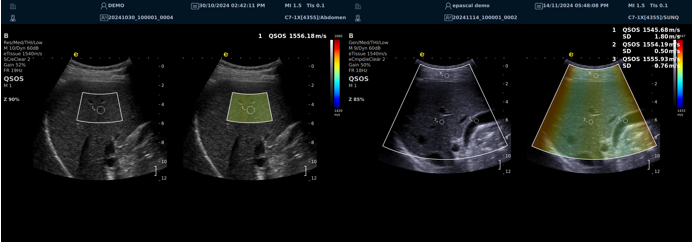

QSOS声速定量成像

测量原理

QSOS声速成像技术利用声波在组织中的传播速度差异性,计算不同位置的声速值,反映组织的物理特性。

成像过程

利用超声探头发射超声波脉冲,分析反射信号的时间延迟,确定声波传播路径和速度,构建声速分布图像。

图像显示

QSOS技术采用彩色编码显示声速图像,不同颜色代表不同声速值,便于医生识别病变部位和测量。

25fb8cb17586b86e5d915a2be3025a2.png

技术优势

?精准定量反映组织特性,成像更敏锐?彩色编码直观显示,轻松发现异常?捕捉声速差异,早期、微小病变更易察觉

肌骨领域的应用

?精准定位损伤部位?判断损伤严重程度?监测肌肉营养?评估肌少症?骨质疏松评估